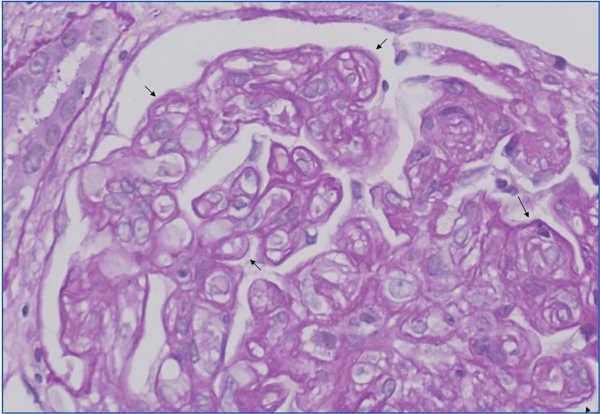

2. Immunopathological evidence of antibody activity: C4d and/or (rarely) immunoglobulins in peritubular capillaries. The C4d deposit must be diffuse and intense (>50%), see Figure 2 and 3.

There are two ways of detecting C4d: indirect immunofluorescence (Figure 2) and immunohistochemistry (Figure 3).

1. Indirect immunofluorescence (in two or three steps) using monoclonal anti-C4d antibody is a sensitive and reproducible method which is easy to interpret. However, it has a number of drawbacks: it does not work on formalin-fixed and paraffin-embedded samples. Therefore, it is necessary to use frozen samples and, furthermore, it is not permanent and deteriorates over time. In our experience, immunofluorescence is the gold standard method for detecting C4d.

Figure 2. C4d deposits. Immunofluorescence